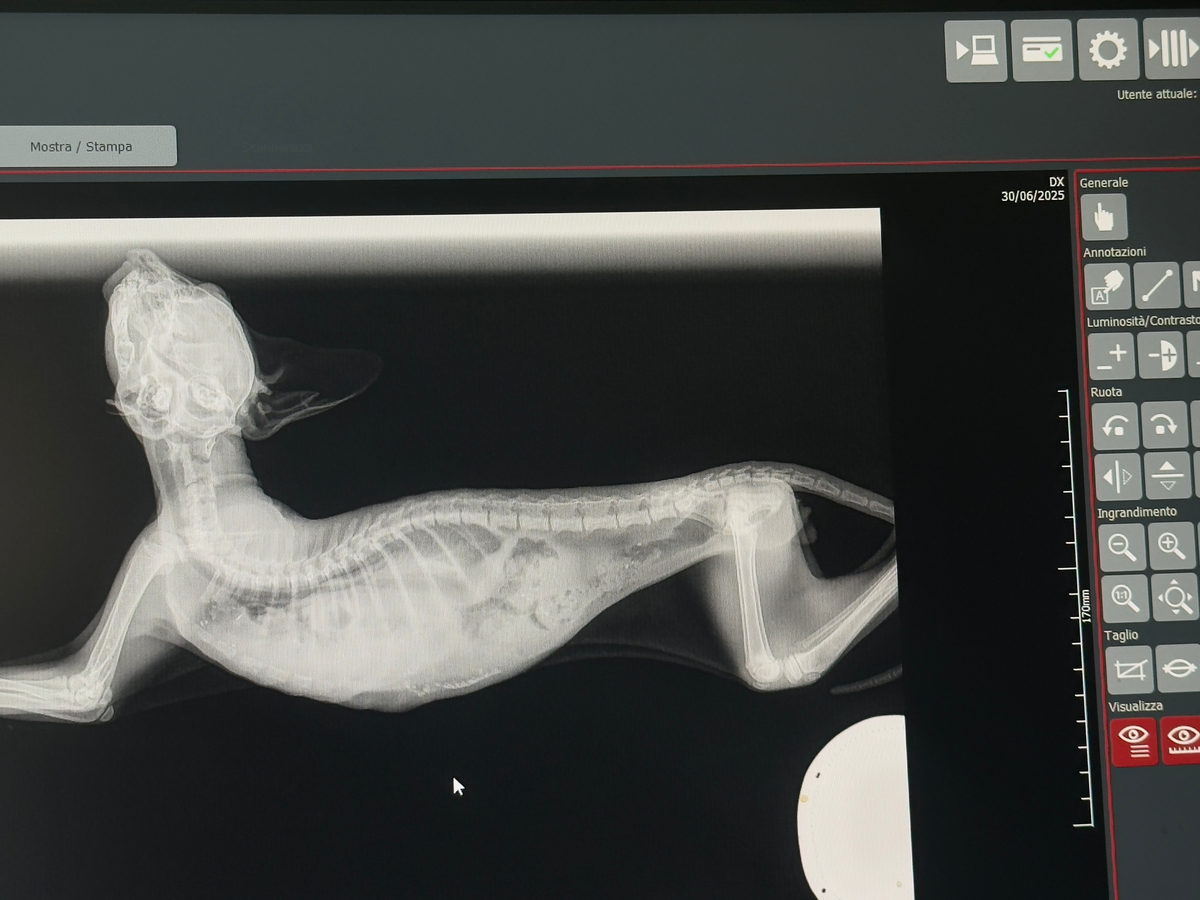

He was breathing slowly and with difficulty… so we took him to the vet. Sadly, we were told he had suffered a severe trauma: in simple terms, his stomach had moved into his chest cavity, putting pressure on his lungs.